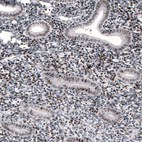

Immunohistochemical staining of human endometrium shows nuclear immunoreactivity in glandular cells and in stroma.